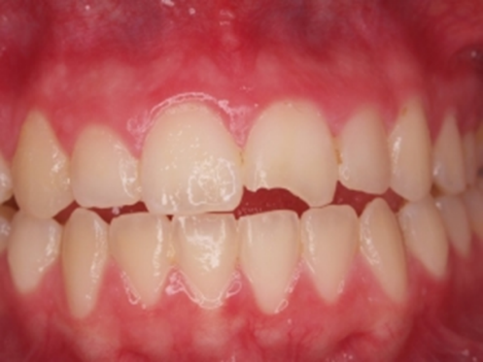

Ben je gevallen, heb je je gestoten of op iets hards gebeten en is er daardoor een stukje van je voorstand afgebroken? Een afgebroken tand ontsiert niet alleen het gebit, een eventueel scherp randje kan ook pijnlijk zijn. Met een composieten facing kan de tandarts je tand zo herstellen dat het lijkt alsof er niets is gebeurd. De behandelingen zijn vrijwel pijnloos. Hoe werkt zo’n behandeling precies?

Figuur 1 Bron: tandvitaal.nl